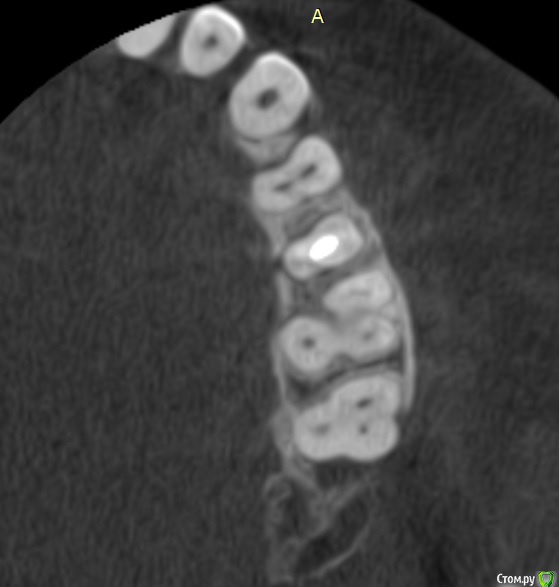

Verasss Опубликовано 8 октября, 2016 Автор Поделиться Опубликовано 8 октября, 2016 КТ от 08.09. Извините, что в таком виде, надо менять ОЗУ. Ссылка на комментарий

DmitrySH Опубликовано 8 октября, 2016 Поделиться Опубликовано 8 октября, 2016 В таком виде КТ малоинформативно. Но гайморита нет. Ссылка на комментарий

Verasss Опубликовано 28 октября, 2016 Автор Поделиться Опубликовано 28 октября, 2016 Добрый вечер! Ещё раз попытаюсь прикрепить скриншоты КТ от сентября. Если качество совсем не устраивает, подскажите, пожалуйста, какие сделать снимки?К сожалению, программа не позволяет вывести снимки на полный экран и заскриншотить в более хорошем качестве. Ссылка на комментарий

Verasss Опубликовано 28 октября, 2016 Автор Поделиться Опубликовано 28 октября, 2016 еще снимки Ссылка на комментарий

Verasss Опубликовано 28 октября, 2016 Автор Поделиться Опубликовано 28 октября, 2016 и еще Ссылка на комментарий